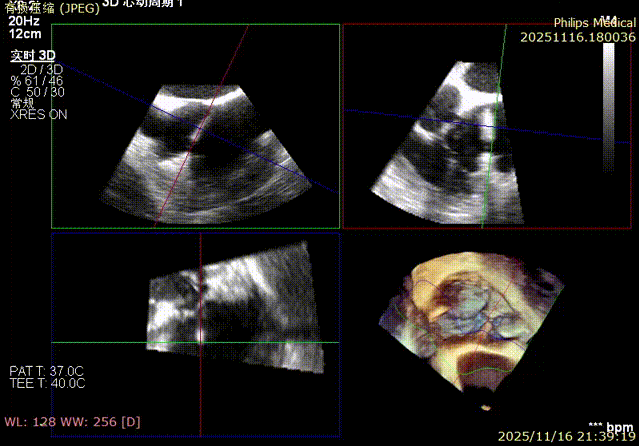

Echocardiographic Assessment: Echocardiography revealed left atrial enlargement. The left atrial appendage (LAA) orifice was 32mm with no thrombus inside. Tricuspid regurgitation was extreme (average vena contracta 18mm). Regurgitant jets were located at the anterior-septal, central, and posterior-septal commissures, with a central gap measuring approximately 13x5.9mm. The annulus was mildly dilated (average diameter 43mm). The tricuspid leaflets showed thickening and degenerative changes.

Immediate intraoperative echocardiographic verification showed that the tricuspid regurgitation area was significantly reduced from a preoperative grade of 5+(pre-op) to 2+(post-op), downgrading the severity from extreme to mild-moderate.

1.Baseline assessment of regurgitation severity.

Comparison of TR regurgitation severity: reduced from 5+ to 2+

preoperative

postoperative

- TR Severity Comparison: Reduced from 5+ to 2+.